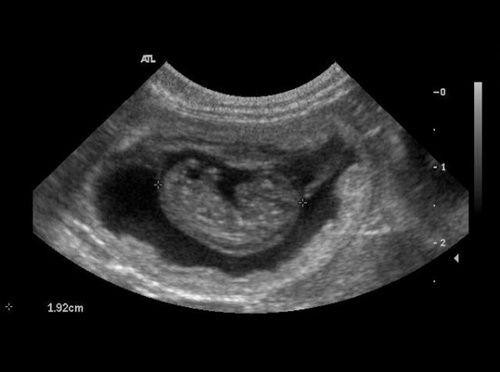

Специальная клиническая диагностика – это использование инструментов и лабораторных исследований. Для постановки диагноза может использоваться рентген, УЗИ, анализы крови и многое другое.